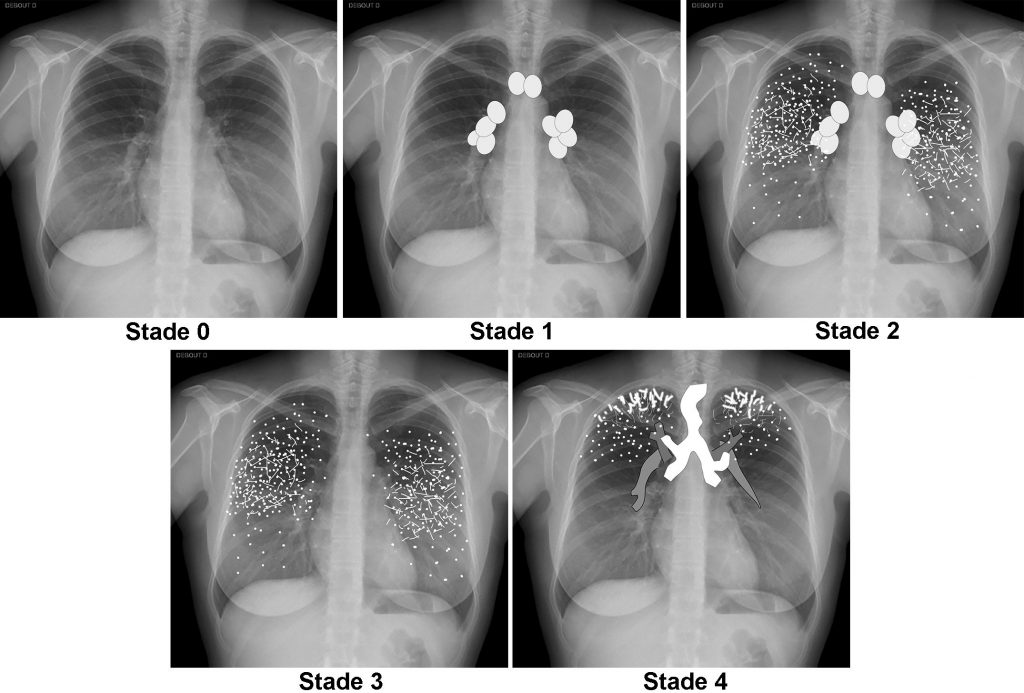

La radiographie thoracique permet de classer la maladie en différents stades (figure 99.1).

Fig. 99.1. Stades radiographiques.

Stade 0 : radiographie normale. Stade 1 : adénopathies hilaires et/ou médiastinales. Stade 2 : adénopathies et syndrome interstitiel. Stade 3 : syndrome interstitiel. Stade 4 : fibrose avec distorsion architecturale (ici, perte de volume des régions supérieures avec ascension des hiles et attraction de la trachée).

Source : CERF, CNEBMN, 2022.

Les signes radiographiques de la maladie sont :

- stade 0 : radiographie normale ;

- stade 1 : adénopathies hilaires ou médiastinales bilatérales (figure 99.2) ;

- stade 2 : adénopathies et atteinte interstitielle (figure 99.3) ; l’atteinte interstitielle se manifeste par un syndrome réticulonodulaire ;

- stade 3 : atteinte interstitielle sans adénopathies ;

- stade 4 : fibrose (figure 99.4) ; les signes de fibrose à la radiographie sont une distorsion architecturale et une perte de volume des lobes supérieurs avec une ascension des hiles et une attraction trachéale.